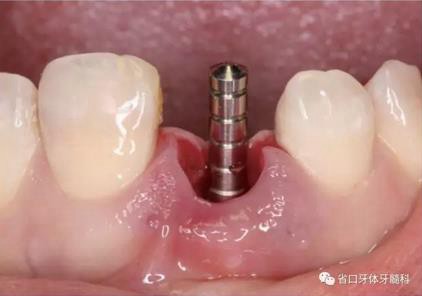

圖15 植入種植體并置入覆蓋螺絲

圖16 跳躍間隙植骨

圖17 跳躍間隙植骨

圖18 測(cè)量ISQ值

(1)微創(chuàng)拔牙及即刻種植:術(shù)前拍攝口內(nèi)照及實(shí)施牙周基礎(chǔ)治療。常 規(guī)消毒鋪巾阿替卡因局麻下微創(chuàng)拔除上頜右側(cè)中切牙,搔刮拔牙窩及根尖肉 芽組織。探測(cè)牙槽骨唇側(cè)骨壁及鄰面牙槽嵴完整,牙齦無(wú)撕裂。不翻瓣下于上頜右側(cè)中切牙缺隙近遠(yuǎn)中中點(diǎn)的腭側(cè)牙槽骨及根方定位,按照逐級(jí)預(yù)備的原則,緊貼牙槽窩腭側(cè)骨壁制備種植窩洞,植入Zimer®3.7mm×13mm TSV種植體1顆,植入扭矩>35N·cm,以O(shè)sstell測(cè)量種植體的ISQ值為68。 種植體平臺(tái)位于唇側(cè)齦緣中點(diǎn)下3mm,與唇側(cè)骨壁內(nèi)側(cè)面形成的跳躍間 隙約2mm,置入Bio-Oss®細(xì)顆粒骨粉0.25g,上愈合基臺(tái)關(guān)閉創(chuàng)口。術(shù)后 CBCT檢查顯示:種植體利用牙槽窩根方骨質(zhì)固位,緊貼牙槽窩腭側(cè)骨壁, 其唇側(cè)面與牙槽窩唇側(cè)骨壁的內(nèi)側(cè)面所形成的跳躍間隙(約2mm)可見(jiàn)顆 粒狀顯影物充填。牙槽窩的唇側(cè)骨壁及唇側(cè)倒凹無(wú)缺損穿孔。